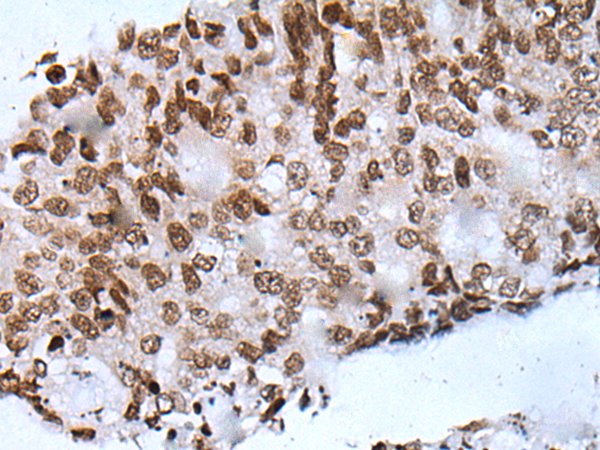

分类: 科研抗体货号: P05998别名: PYM; WIBG应用: IHC反应种属: Human, Mouse